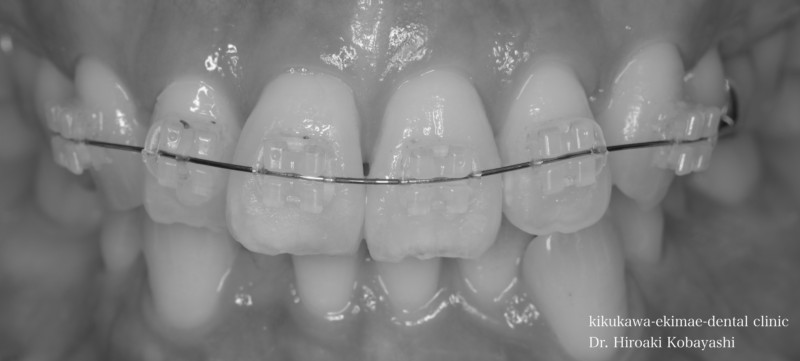

歯並びを気にされて来院されました。見た目改善を目的にワイヤーによる部分矯正を希望されました。 ブラケット装着用のマウスピースを作り、ブラケット装着を行います。   弱い力をかけながら、ワイヤーにより歯を動かします。強い力を急にかけると歯の根が吸収されてしまいます。なので弱い力で歯を動かすことによって根への負担が少なく歯根吸収のリスクが少なくなります。               6ヶ月程度で歯の並びを改善することができました。   before after